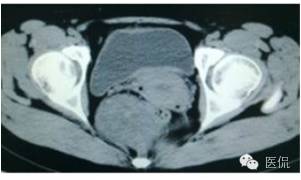

增强静脉期(CT值62HU)